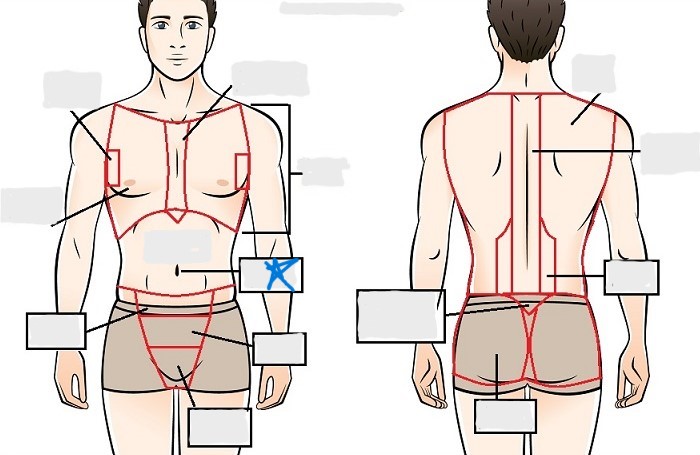

axial

cephalic

occipital

frontal

otic

orbital

nasal

oral

mental

cervical

dorsal

scapular

vertebral

lumbar

sacral

gluteal

thoracic

sternal

mammary

axillary

abdominal

umbilical

pelvic

inguinal

pubic

perineal

appendicular

acromial

brachial

antecubital

olecranal

antebrachial

carpal

manus

coxal

femoral

patellar

popliteal

crural

sural

peroneal

calcaneal

plantar